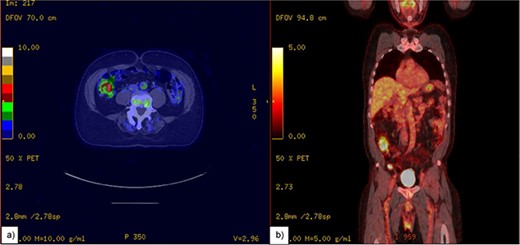

A 72-year-old male, who had previously been diagnosed with MCL in 2021 and had undergone R-CHOP therapy achieving remission, presented to the Emergency Department with a history of right lower quadrant abdominal pain, lightheadedness, and persistent nausea for over a week. Upon initial evaluation, computed tomography (CT) (Fig. 1) raised the suspicion of a potential volvulus. However, upon transfer to the operating room, a markedly distended appendix, accompanied by substantial lymphadenopathy affecting the mesoappendix, was unveiled (Figs 3–5). An appendectomy was subsequently performed, and the excised specimen was promptly dispatched for pathological examination, which confirmed the presence of MCL.

An image of the mass (pointing arrow) on (a) axial view showing Swerling sign, (b) coronal view.

MCL often starts with lymph node enlargement and can spread to the bone marrow, liver, and gastrointestinal tract, especially the colon. It rarely affects the appendix, typically through nearby ileocecal involvement [4, 5]. In our case, a 1.4 cm appendiceal mass was found on a positron emission tomography CT (PET-CT) scan a year prior to presenting with the symptoms, but follow-up was not pursued until the patient presented with pain and obstructive symptoms due to an enlarged appendix, confirmed by CT to be a “swirl sign” indicative of volvulus (Figs 1 and 2). The appendix measured 5 cm in width and 16.5 cm in length (Figs 3–5).

We report a rare case of MCL in the appendix, where the patient was presented with abdominal pain and a distinct “swirl sign” on a CT scan. The appendix was significantly enlarged, measuring 5 cm wide and 16.5 cm long, leading to appendiceal torsion. This is the first documented instance of MCL causing appendiceal volvulus with a swirl sign on CT. The rarity of this presentation, along with vague symptoms, caused a diagnostic delay. This highlights the need for more understanding and documentation of such cases to improve diagnosis and treatment. Managing MCL in the appendix differs from other lymphomas in this area.